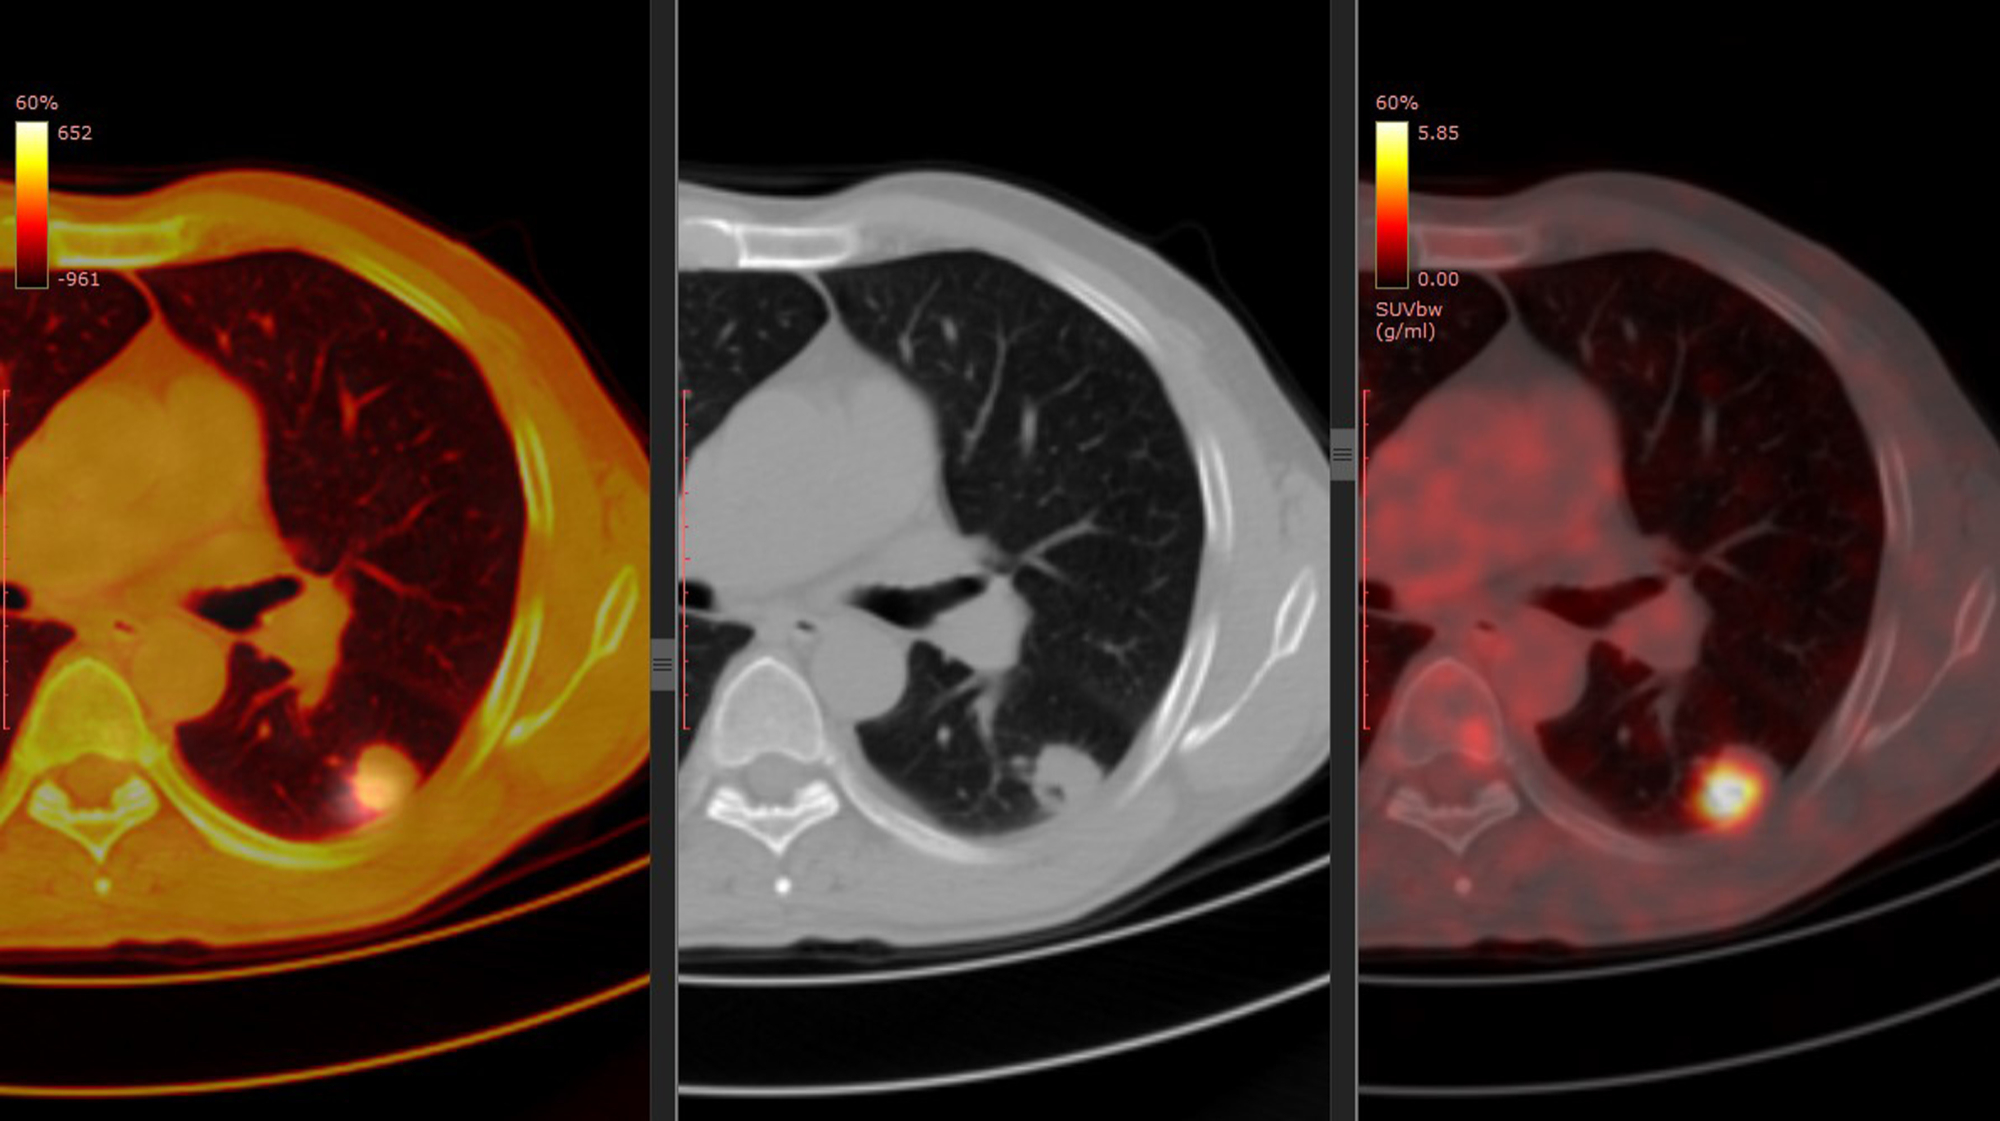

Centralized Imaging in Early Phase Oncology Trials

• Scientific considerations in early‑phase oncology and the critical role of BICR (Blind Independent Central Reading) in ensuring high‑quality, unbiased imaging data.

• How BICR rolling reads enhance safety monitoring, particularly in studies with elevated risk of interstitial lung disease (ILD) in ADC drug.